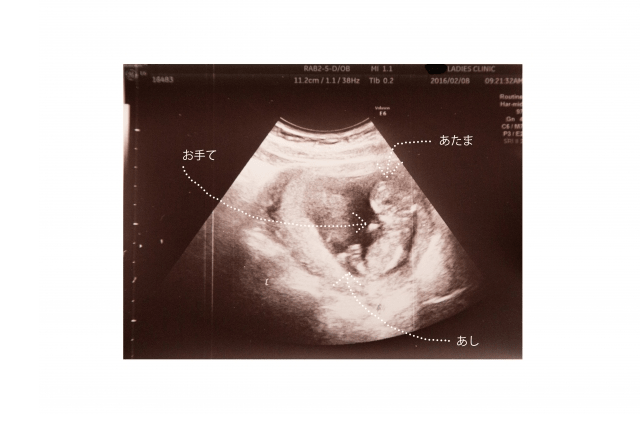

しかし、あくまでも赤ちゃんの様子を見ること

が出来るのは、超音波検査によるお腹の外から

のものです。

そうなると、性別判断が出来るようになるのは、

妊娠16週目以降と言われています。

このように、赤ちゃんの性別を判断するのは、

超音波検査であるため、赤ちゃんの様子が、

明確に分かるものではありません。